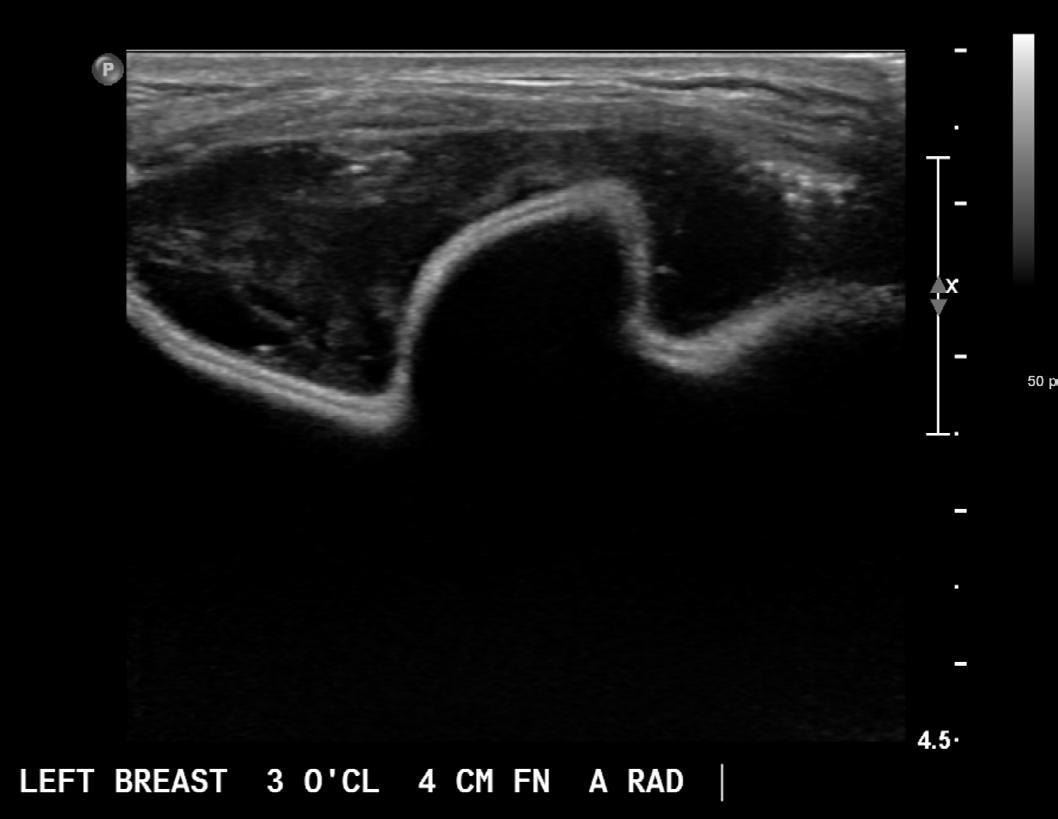

The job of a remote radiologist is not easy. Our remote radiologists cover up to 12 sites a day, with cases scheduled independently at each site. Radiologists must be able to manage multiple cases at the same time while ensuring that technologists complete their cases in the allotted time. This workload can be very challenging even with a good system. Not all radiologists can make the transition to managing remote diagnostic cases. Successful radiologists must have an organized process to make sure they are not mixing up cases or forgetting to dictate reports. I write my list of patients for each site on a wipe-off board in the morning (Figure 1). I place a check mark next to a patient’s name when the technologist sends me the images and then erase the name once I have dictated the report. I also dictate as I go, so I have the history, mammographic findings, and requested ultrasound images noted in the report when additional images are sent back to me for review. I don’t have to figure out who the patient is, what is going on, or what I wanted done, because it is all documented. This system saves time and limits mistakes.

Figure 1

Our practice has developed programs to streamline the process. Our scheduling system assigns each radiologist their sites for the day (Figure 2) so the radiologists and technologists know who they will be working with that day. The physician relations team is also available to reassign cases to different radiologists to manage overbooking or emergencies, if needed. Technologists communicate with radiologists through our messenger system in the picture archiving and communication system (PACS). They send a link to the case and a short blurb describing the clinical history and indication. Instructions are then sent back to guide the workup (Figure 3). We have an online protocol available to the technologists. Each radiologist has a page in the protocol that outlines what they want done in a standard set of situations. This allows technologists who have not previously worked with a radiologist to review the radiologist’s expectations. We also tailor clinical schedules to individual radiologists. More efficient radiologists can cover more sites and more cases. Radiologists who are less efficient aren’t pushed to read more than they are capable of or comfortable with. We also have access to other breast radiologists for consultations through the messenger system in the PACS.

Ultrasonography is clearly the biggest concern for radiologists looking to start a remote diagnostic program. Dedicated breast sonographers are critical to a successful program. The technologist-radiologist relationship is very important, so we

try to schedule our radiologists consistently to cover the same sites on a regular basis so trust can grow over time. Giving technologists detailed instructions and descriptions of what you are looking for is helpful. Solving problems may involve using cine clips, describing landmarks, using three-dimensional ultrasonography, suggesting strategies to optimize image quality, or explaining to the technologist what you would do if you could actually scan the patient yourself. We also have lead technologists who can help troubleshoot issues if needed. Most importantly, though, when referring a patient for remote ultrasonography, radiologists should have a plan in case no ultrasound correlate is found, just as if they failed to find a correlate on in-person realtime examination.